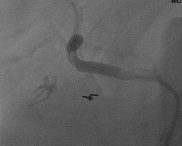

Sequential drug-eluting stents were placed and post-dilated with a good result (Fig 2, 3).

The patient had an uneventful overnight stay in the hospital and has remained free of symptoms at four months post-procedure.